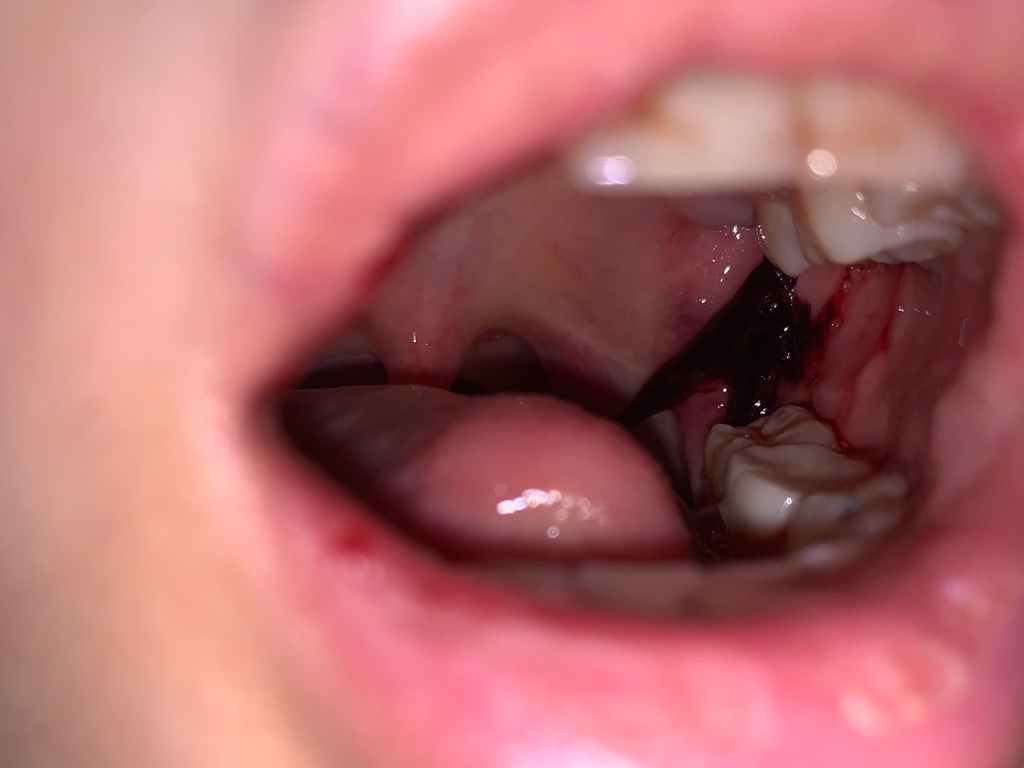

사랑니 발치 이틀 됐는데 사진처럼 큰 피덩어리가 생겼어요 이거 괜찮나요?

이틀전에 위아래 둘다 발치했는데요. 자고 일어났더니 사진처럼 되있어요ㅠ 위아래 잇몸에서 나온 피덩어리가 합쳐져 있어요ㅠㅠ 피덩어리 한줄기는 목구멍으로 넘어가려고 하고 있고요ㅠ 손가락 한마디 크기인거 같아요 이거 이대로 놔둬도 괜찮아요?

일어나서 요플레 먹고 약먹고 한시간 반 정도 지나니까 아래 사진 처럼 됐어요. 여전히 위아래 사랑니자리 잇몸에서 나온 피덩어리는 합쳐져 있어요ㅠ 병원 가봐야 할까요? 안 가도 괜찮을까요?

피떡(혈전)이 생기고 있는 과정인데 처음 지혈 시 충분히 거즈로 압박지혈 하지 않았거나 출혈이 완전히 멈추지 않았는데 거즈를 좀 빨리 뺀 경우 저렇게 퍼질 수 있습니다. 피떡을 굳이 일부러 제거하거나 빨아들일 필요는 없습니다. 본인 피이므로 목으로 넘어가서 어쩔 수 없이 흡입하게 되는 경우도 큰 문제는 없습니다. 멸균 거즈로 다시 잘 누르고 거즈 밖으로 튀어나온 피떡만 조금 제거해주는 것 정도는 괜찮을 것 같습니다.